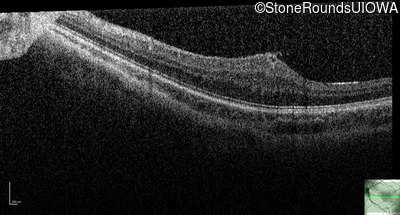

This 9 year old male was noted to have some crossing of his eyes at 2 months of age and the eye exam which followed identified a retinal lesion in the right eye. When he was six years old an epiretinal membrane was noted in his left eye. Two years later it was decided that it was a thin hamartoma in that eye as well. He underwent neuroimaging at age 7 which identified bilateral acoustic neuromas.

| Age at visit: 14 years |